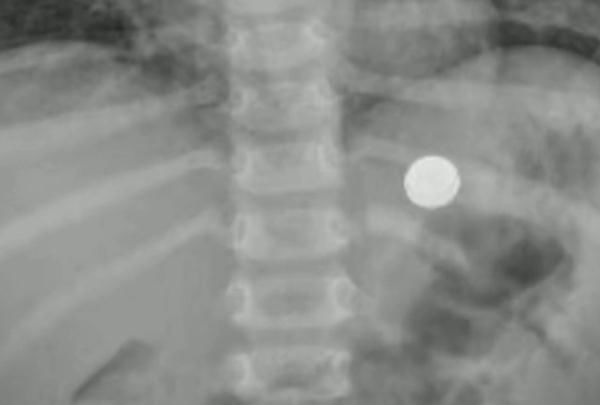

在其他医院的检查结果显示

他的胃内的确有异物

文章插图

一番检查后

医生马上进行了全麻手术

从孩子的胃里

拿出了一枚直径约1厘米的纽扣电池

而它也引发

孩子的胃部多发溃疡

“很庆幸的是,这颗电池在体内是一天,时间比较短;当时取的时候也比较顺利。”